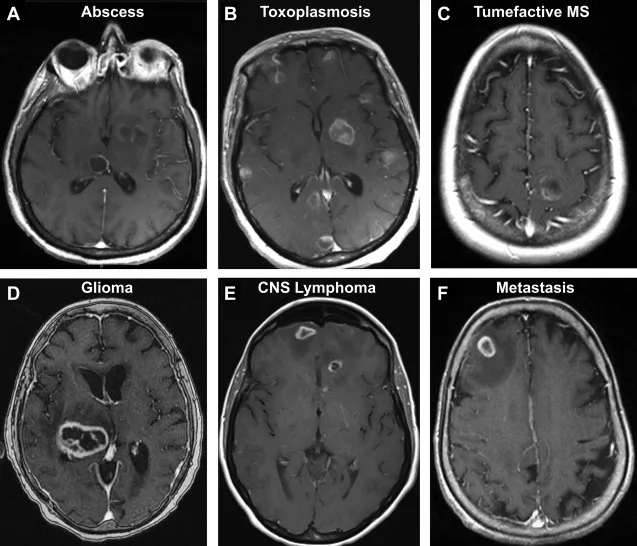

- Imaging: Ring-enhancing lesion on CT/MRI with contrast.

- Imaging: Multiple ring-enhancing lesions, often in basal ganglia.

- Imaging: "Swiss cheese" appearance; cysts in various stages (viable, calcified).

⭐ In an HIV+ patient with multiple ring-enhancing brain lesions, the main differential is Toxoplasmosis vs. Primary CNS Lymphoma. A trial of pyrimethamine and sulfadiazine is diagnostic and therapeutic.

- Brain abscesses and Toxoplasmosis both present as ring-enhancing lesions on imaging, but Toxoplasmosis is more common in HIV/AIDS.